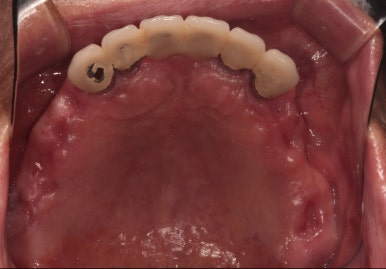

왼쪽: 위턱 교합면, 오른쪽: 아래턱 교합면

대부분의 어금니를 뽑고나서, 약 2달 후 구강내 사진입니다.

앞니만 남게 되었습니다...

위는 총 6개의 앞니가, 아래는 총 5개의 앞니가 남았습니다.

이를 뽑고 임시 틀니를 사용하시면서 2달 정도 기다리시게 되면, 위에 보시는 것과 같이 어느 정도 단단해진 잇몸이 생기게 됩니다.